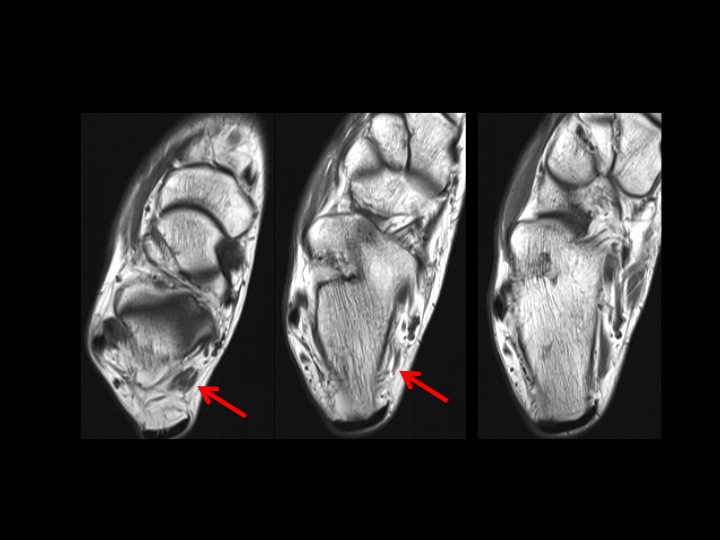

The accessory muscle in question (red arrows) appears to arise from the posterior aspect of the distal fibula. From cranial to caudal it lies lateral then posterolateral to the FHL and inserts onto the quadratus plantae. This does not conform to any of the reported accessory flexor muscles I can find. What would you call it? It shares the same insertion as the FDAL, but does not course superficial to the Posterior Tibial NV bundle. (Did you notice the peroneus quartus? She seems to have too much of everything!) Reference article.